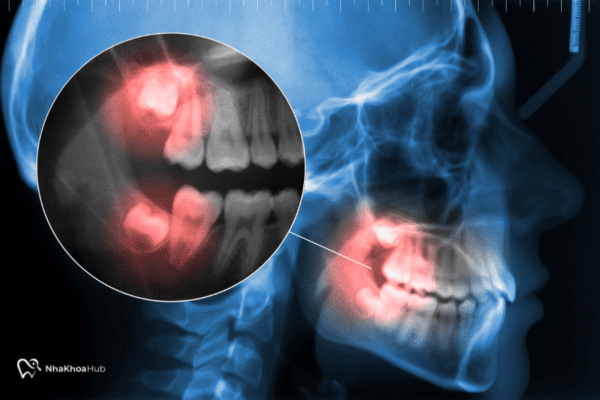

Phẫu thuật lệch khớp cắn bao nhiêu tiền? Bảng giá chi tiết